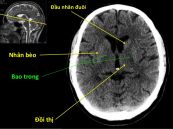

Xuất huyết nhân bèo trái là một trong những bệnh lý rất nguy hiểm. Để hiểu rõ hơn mời các bạn cùng tham khảo bài viết ngay dưới đây nhé!